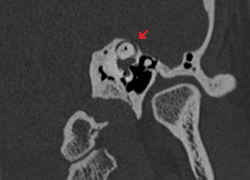

A síndrome de deiscência de canal semicircular superior, ou síndrome da deiscência do canal semicircular superior,[1] é uma condição patológica rara, descrita pela primeira vez na literatura médica em 1998, que consiste em perfurações no canal semicircular superior, dentro do ouvido.[2]

A principal causa da síndrome é o desgaste da camada óssea que recobre o canal semicircular superior. [3]